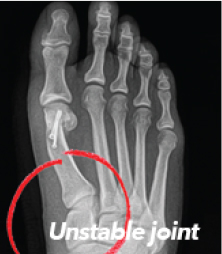

What Does A Correction Look Like On X-Ray?

xray Normal Foot

xray Traditional 2D Surgery

"Cut & Shift" approach leaves an unstable joint

xray Lapiplasty® 3D Bunion Correction™

Alignment is restored & unstable joint is permanently secured